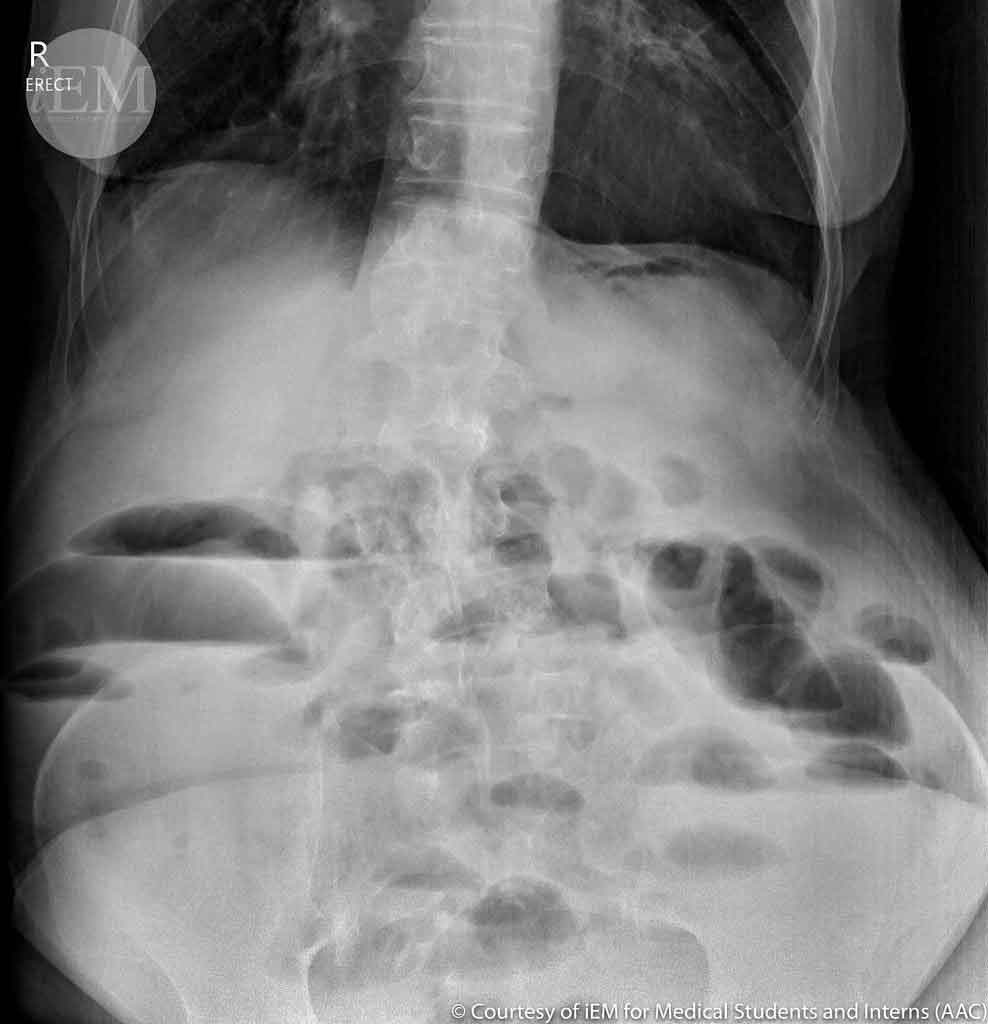

Intestinal obstruction occurs when the normal flow of digestive contents is partially or completely blocked in the small or large intestine. This is a serious condition that requires prompt medical evaluation and timely intervention to prevent complications like bowel ischemia or perforation.

Emergency & Non-Surgical Management

When the bowel is not strangulated:

• Nasogastric decompression to relieve pressure

• Intravenous fluids and correction of fluid/electrolyte imbalances

• Close monitoring for signs of resolution or progression